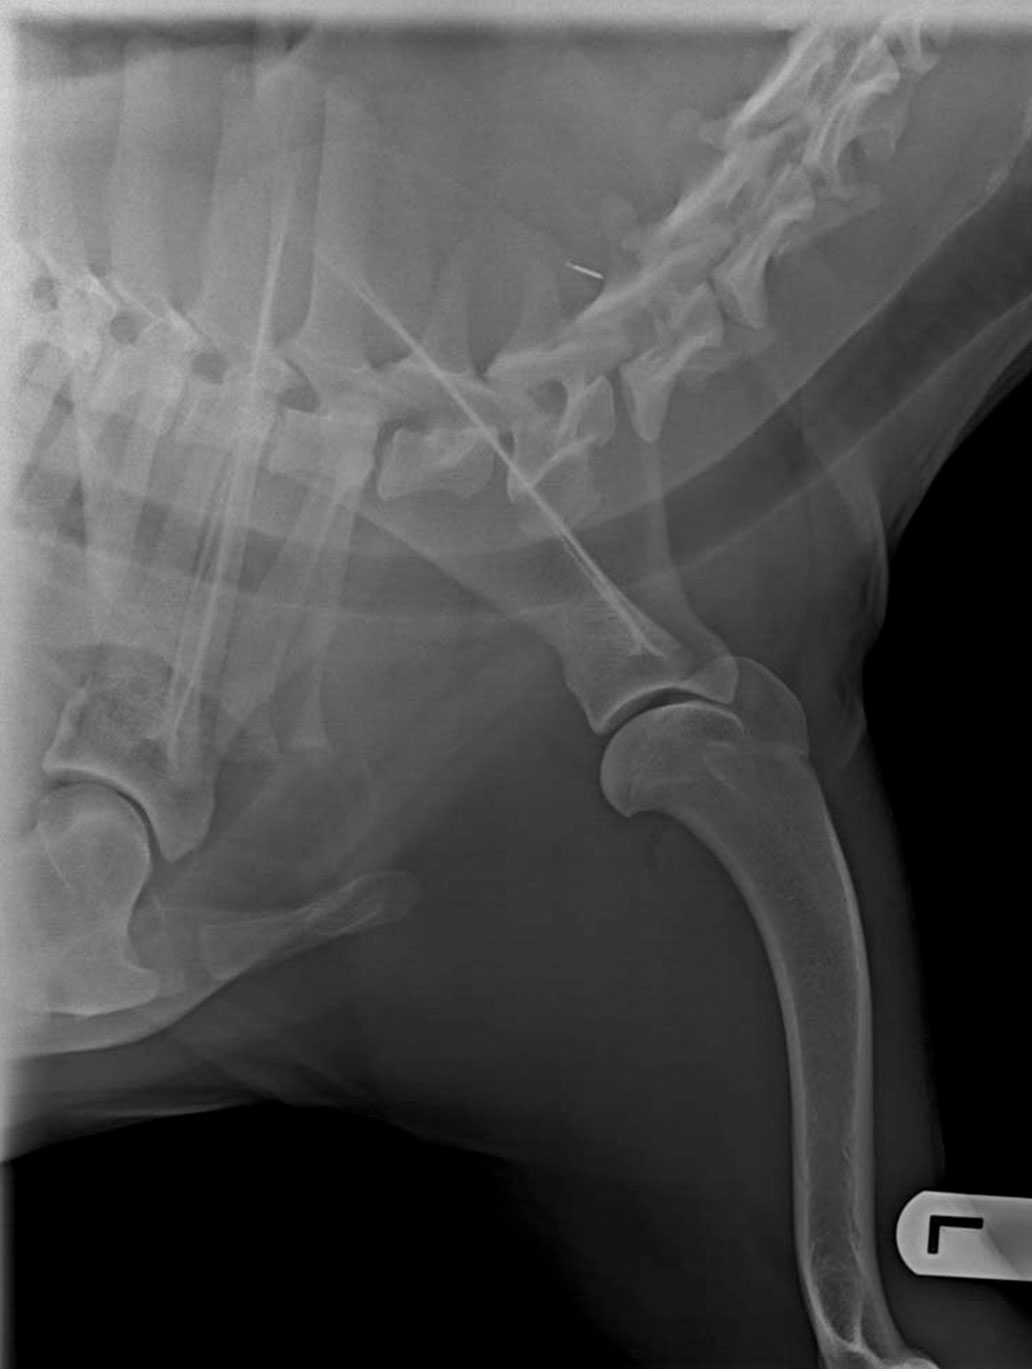

ED Grad 0

ED Grad  3